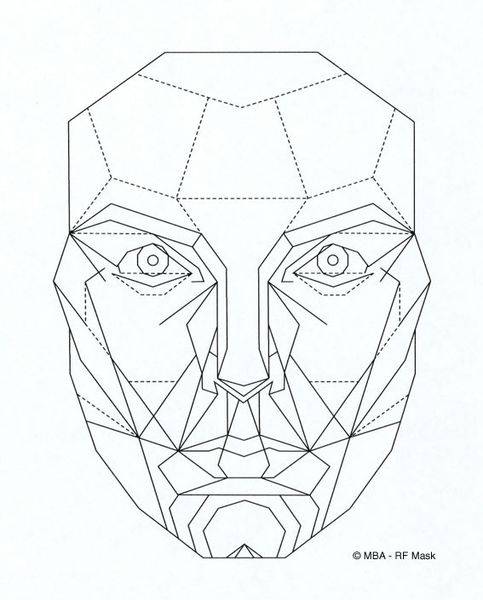

В качестве экспресс-анализа лица можно использовать «десятиугольную золотую маску красоты», которую создал американский челюстно-лицевой хирург Маттиас Марквардт. Маска универсальна для людей всех рас, культур и мест проживания. Она отображает идеальные черты лица и актуальна для любого возраста [1]. Этот анализ не заменит инструментальной диагностики, но может быть полезен на начальном этапе, так как гармоничность лица — показатель функционального здоровья.

Десятиугольная золотая маска красоты